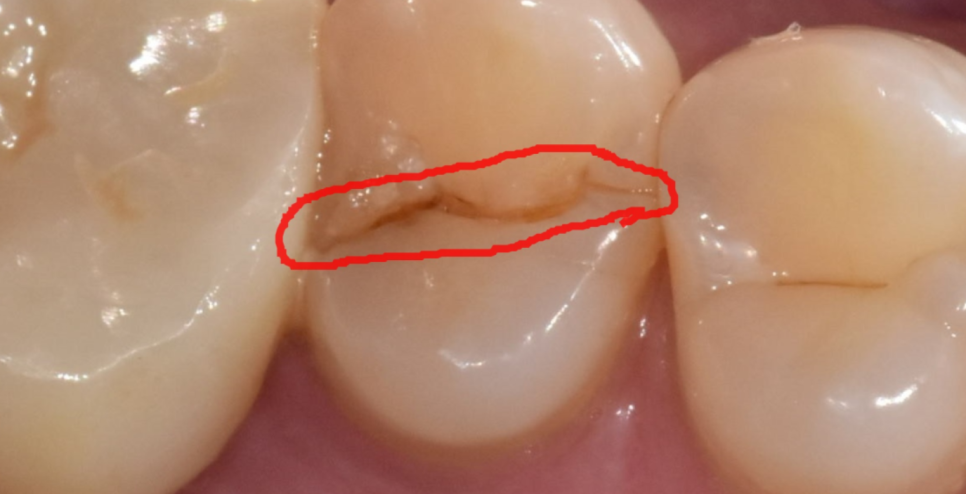

문제의 오른쪽 윗부분을 보는데..

딱 보입니다.

어금니 쪼개짐이 보입니다.

정확히 절반으로 어금니 쪼개짐

발생했습니다.

확대해서 보면

이런 모습이죠